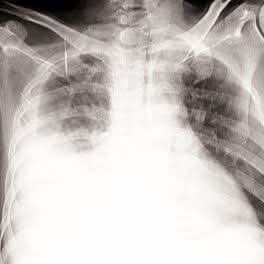

قال الدكتور وهاج المقطري:شاب ٢٤ عاما، اشتكى من ألم في صدره الأيمن منذ اسابيع، ظنه في البداية ألم عضلي بين الأضلاع، لكن مع مرور الأيام ازداد الألم وظهر عنده ضيق في التنفس فتوجه إلى أحد المستشفيات لإجراء الفحوصات،.

أظهرت الأشعة وجود تجمع سوائل في الجنب الأيمن فتم ترقيده وسحب السائل منه وأُعطي مضادات حيوية واسعة الطيف،، وتحسنت حالته لكن بعد أسبوع عاد الألم وضيق النفس من جديد،وأُظهرت الأشعة أن السوائل قد عادت الى صدره فطُلب منه إعادة سحب العينة لكنه رفض ثم جاء إلي..

شاب سليم لا يعاني من أي من الأعراض الكلاسيكية للسل، ولم يشتكي من شئ طوال حياته، ونتائج فحص السل Mantoux و (QFT) وحتى PCR كانت سلبية وتحليل السائل الجنبي لم يظهر سل ولا خلايا سرطانية،،.!!

والحقيقة لست ادعي انني كنت ساطلب منه القيام باجراء خزعة جنبية (وهو الفحص ذو أعلى عائد تشخيصي في هكذا حالات) للتأكد اكثر من السل لولا انه قال ان والدته ماتت بالسل،،زاد دافعي أكثر علمي بان السل الجنبي احد اصعب الحالات تشخيصا فحتى فحص PCR قد يفوت التشخيص بسبب مايعرف ب (paucibacillary nature)،، فطلبت منه فورا اجراء خزعة جنبية وأقنعته بصعوبة بضرورة اجراءها..!!

ثم جاءت النتيجة بعد فترة إيجابية بوضوح مؤكدة إصابته بالسل الجنبي (Pleural tuberculosis) رغم سلبية كل الفحوصات السابقة،، وتم تحويله إلى مركز الدرن وبدأ بالعلاج الخاص بالسل وفي غضون شهر ونصف بدأ التحسن يظهر عليه بوضوح..!!